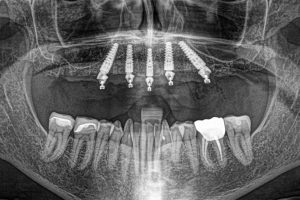

The All-on-4 dental implant procedure is a life-changing solution for missing teeth. This permanent and

The All-on-4 denture implant procedure is a revolutionary dental solution if you need full-arch restoration.